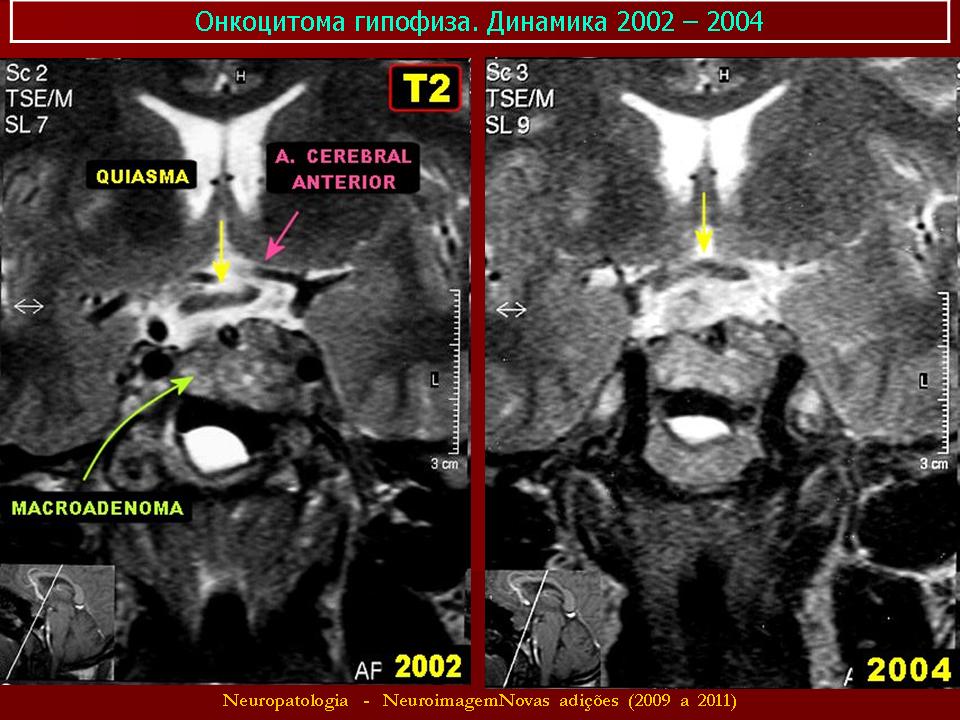

Гормонально-неактивные аденомы - аденомы, патогенез нарушений при которых заключается в увеличении объема опухоли, расположенной в передней доле гипофиза и в воздействии этого объема на гормонально-активные клетки гипофиза, что приводит к их нарастающей атрофии. Наряду с этим опухоль воздействует на анатомические образования мозга - зрительные нервы, хиазму, черепные нервы, гипоталамус, внутренние сонные артерии. К этим опухолям относятся хромофобная аденома и онкоцитома.

11. Онкоцитома.